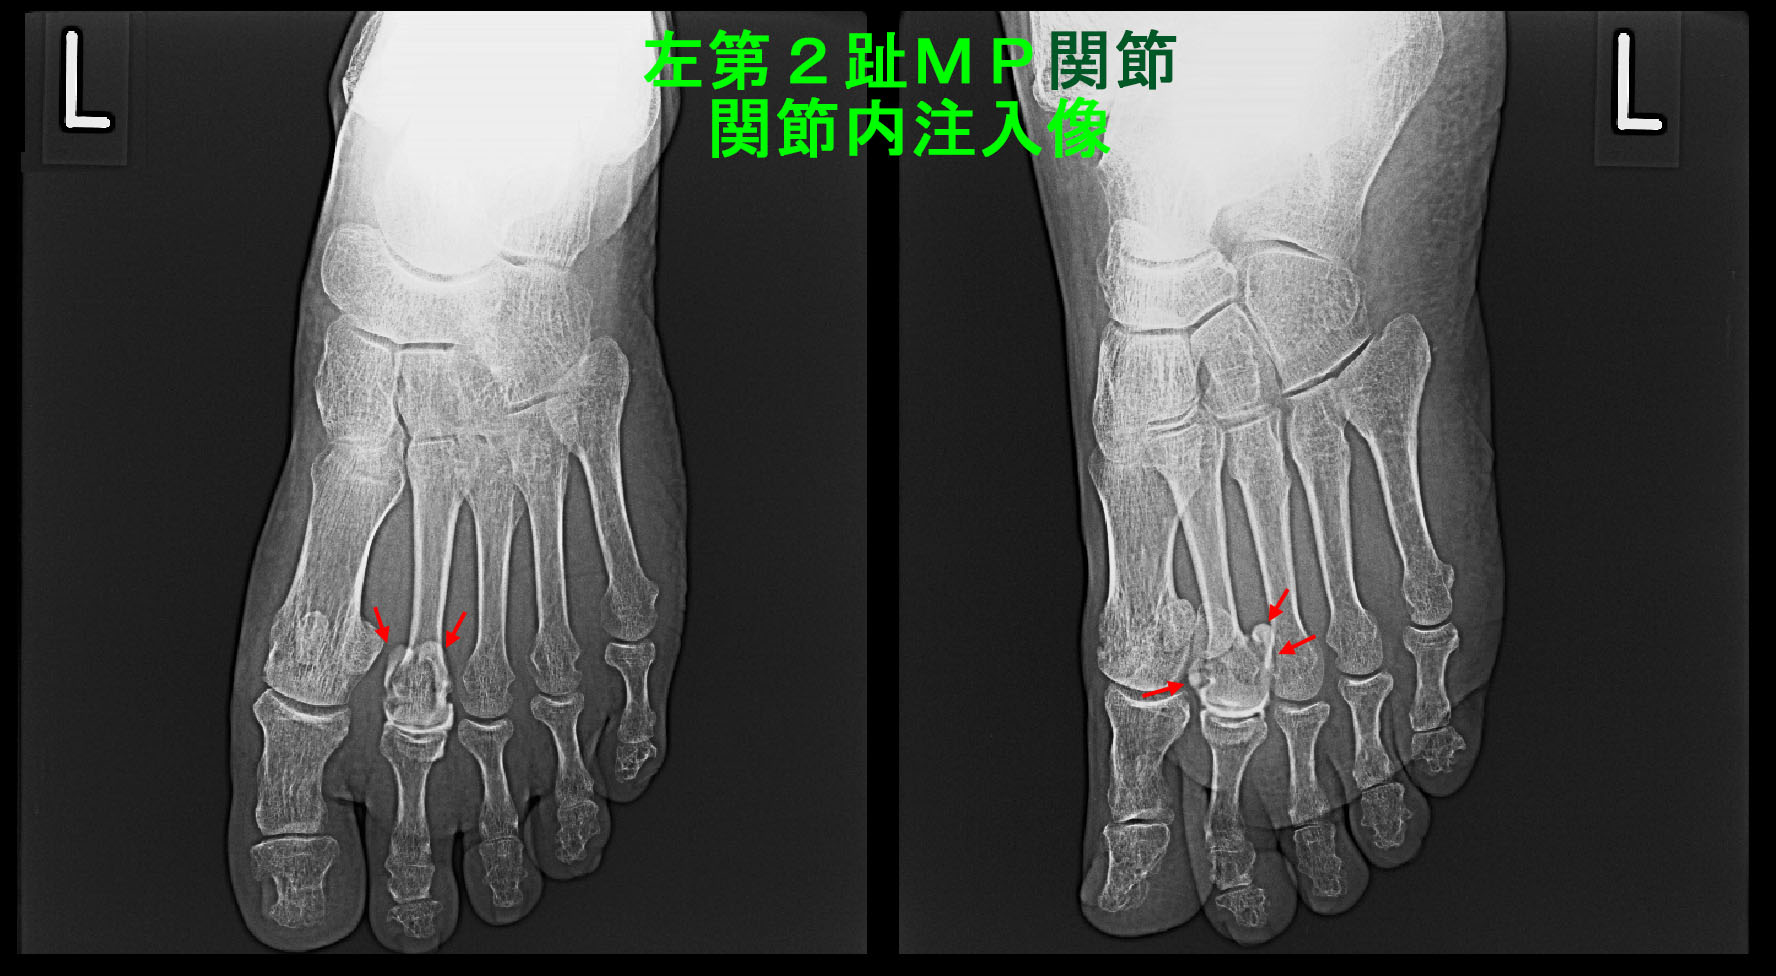

76才男 Xp2.jpg

以後、患者さんは再診されなかったため、3週後の10月1日に電話で経過を確認すると、当初の痛みを10とすると2~3に軽減していて、屋内歩行は問題ないが、革靴を履くと痛みがあるということでした。私がもう1度関節内注入を行うとより改善する可能性がありますと伝えました。10月7日に再診され、2度目の右第2足指MP関節内ステロイド注入を施行しました。その後も受診されなかったため、12月30日に電話をかけると、2回目の関節内注入後、3日で症状は治癒したとのことでした。